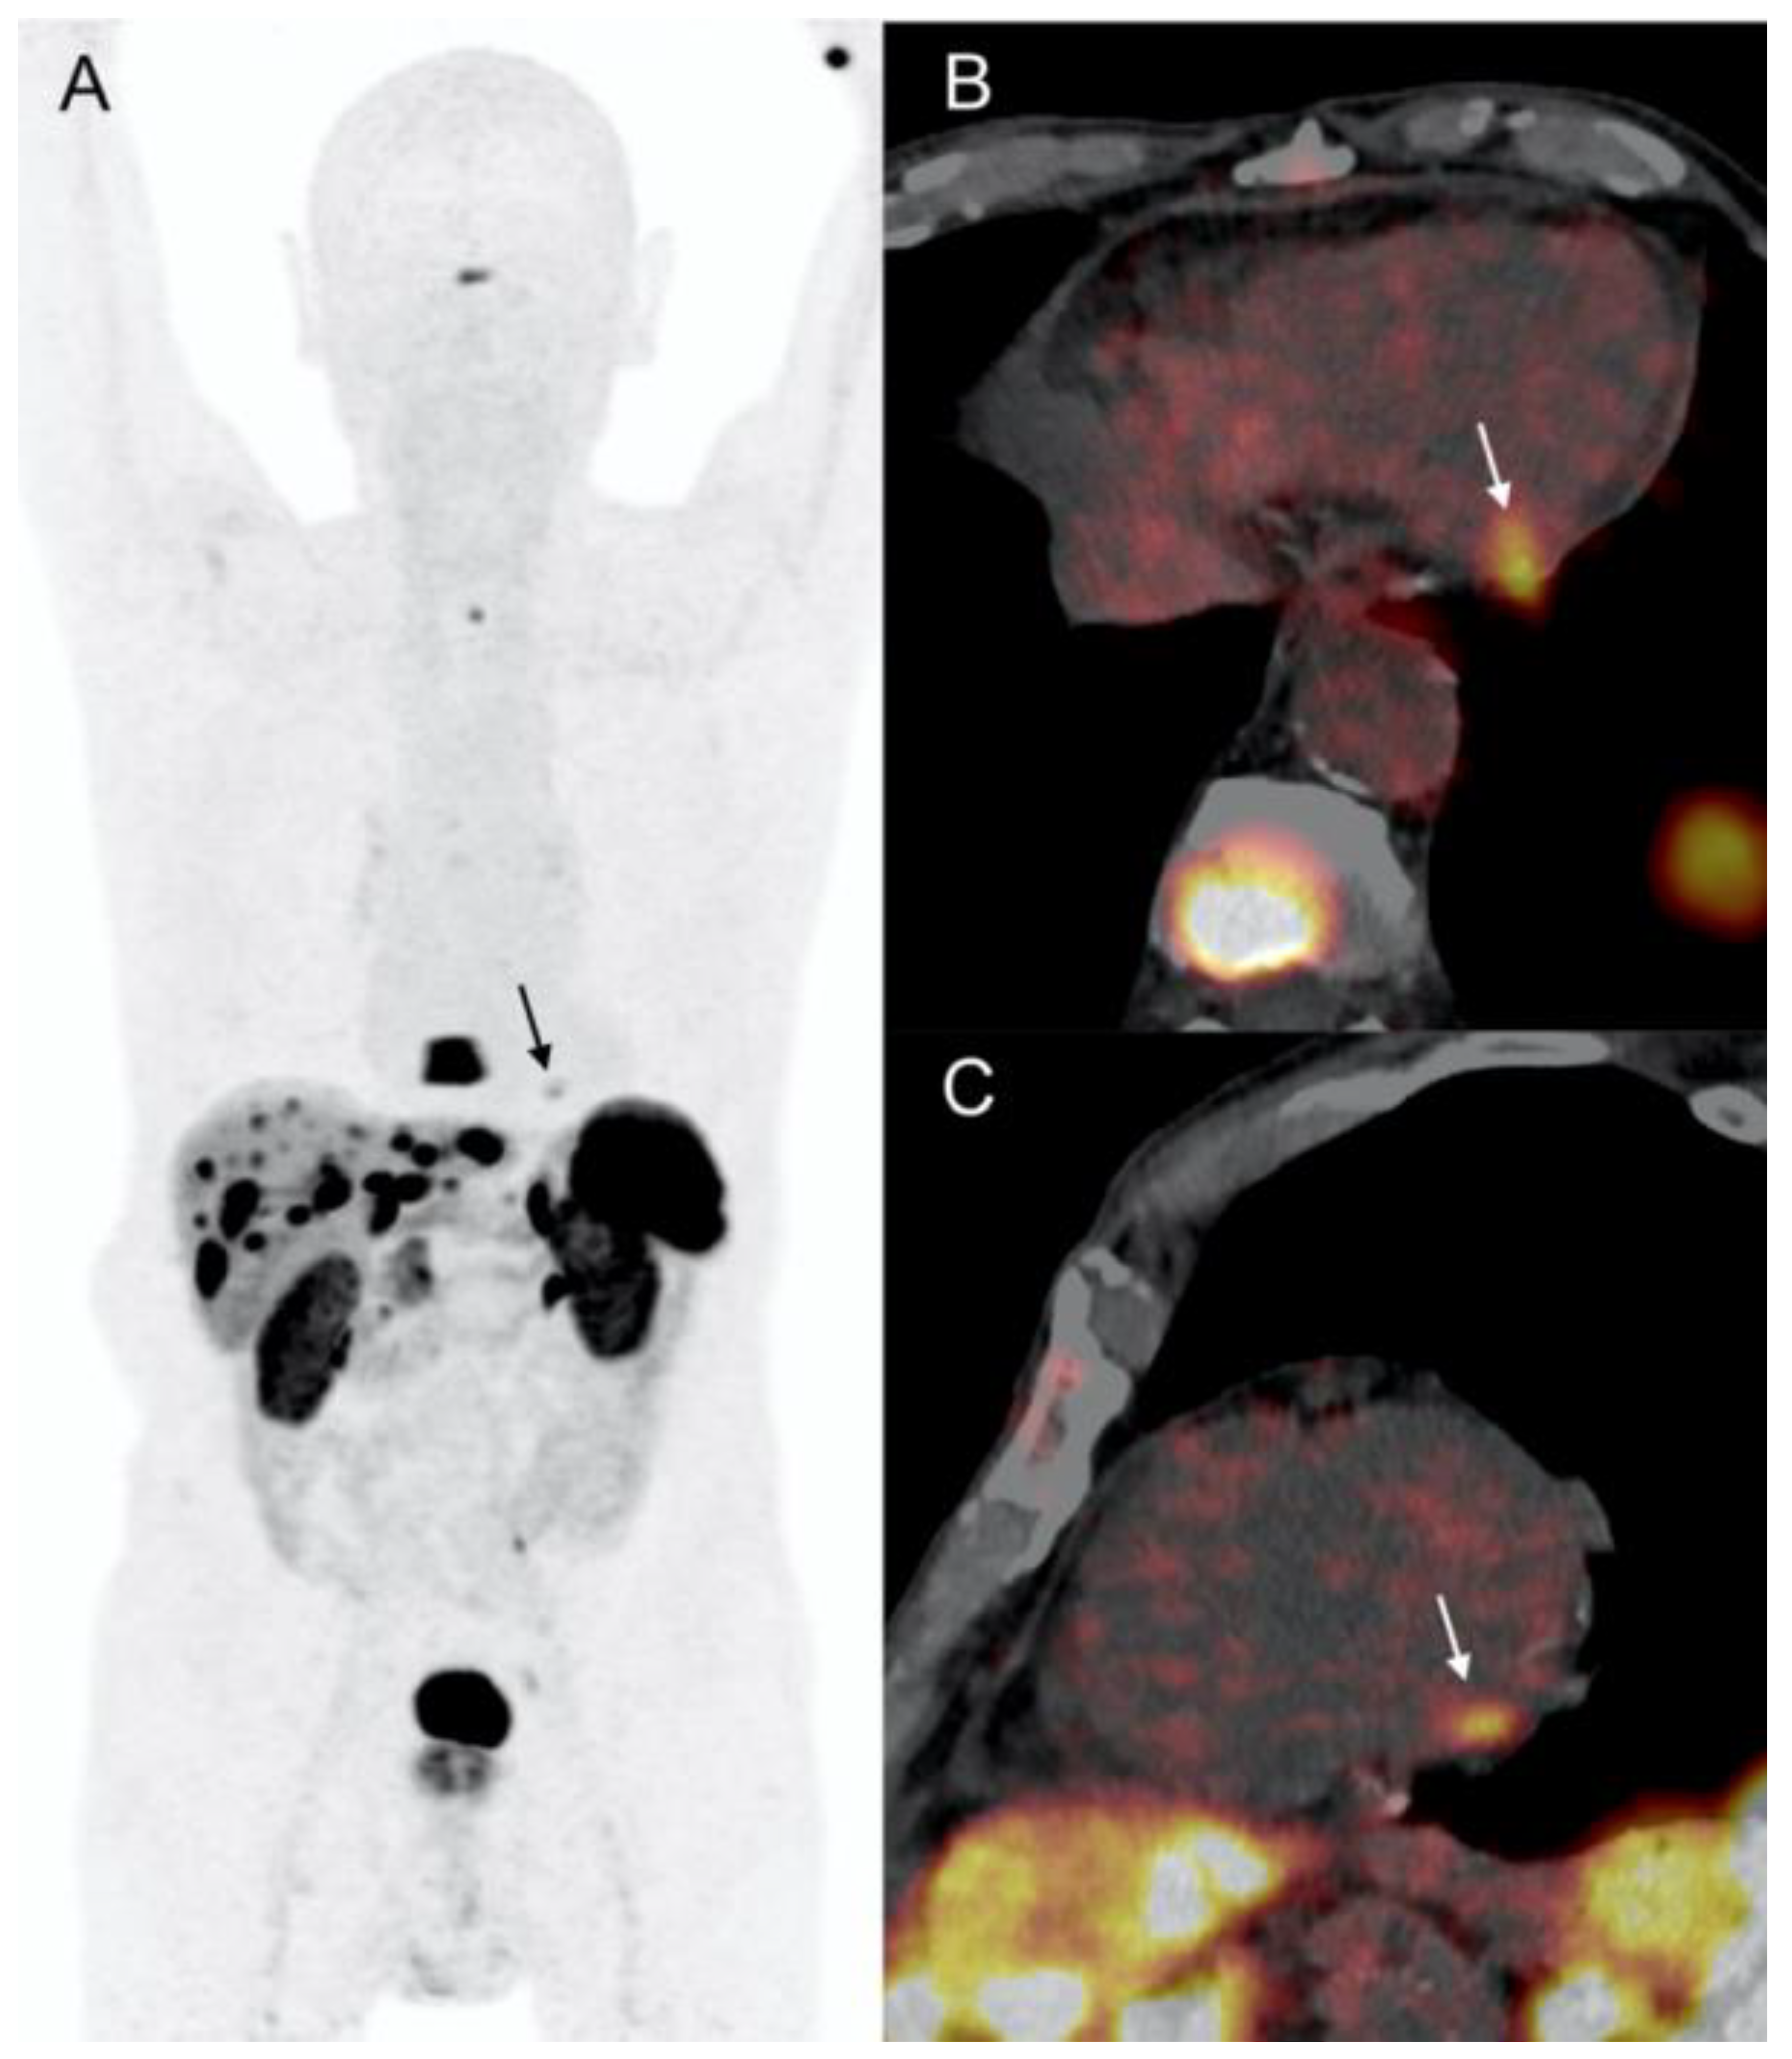

2.4. Patient 4

- 68Ga-DOTA-peptides and 18F-DOPA PET/CT are highly sensitive and specific for the initial diagnosis of CMs, which are usually detected incidentally during routine investigations;

- CMR and Cardiac-CT enable high-resolution, multiplanar imaging crucial for accurate anatomic localization, mass mobility assessment, and tissue characterization for noninvasive diagnosis confirmation;